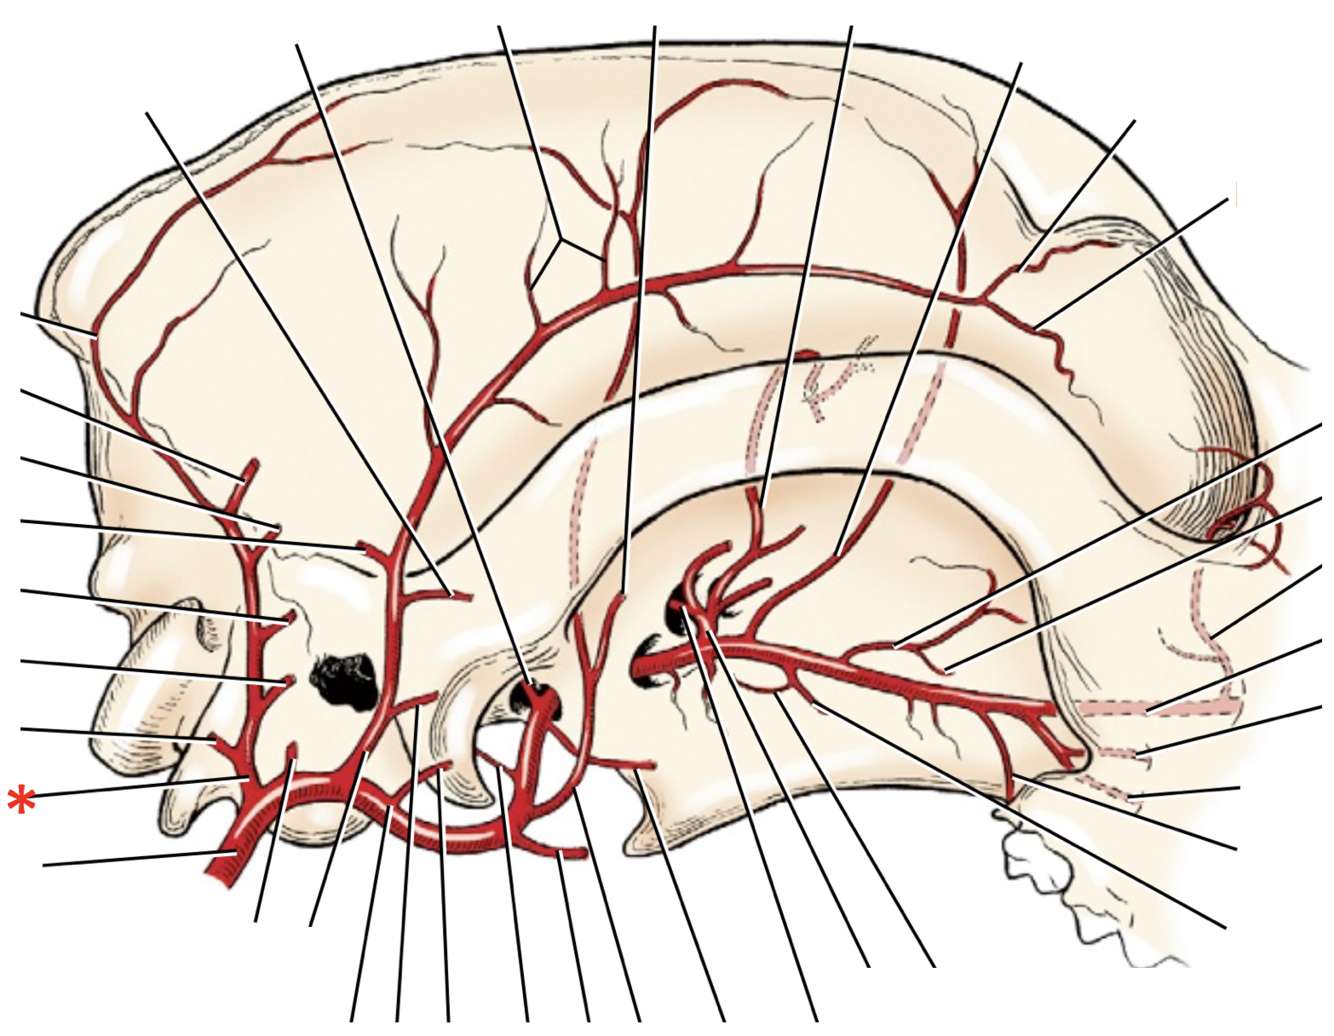

A. lingualis

A. facialis

A. maxillaris

A. auricularis caudalis

A. occipitalis

A. sublingualis

A. temporalis superficialis

A. facialis

A. cariotis externa

A. maxillaris

A. auricularis caudalis

A. lingualis

A. facialis

A. laryngea cranialis

A. maxillaris

A. occipitalis

A. carotis externa

A. laryngea cranialis

A. lingualis

A. facialis

A. sublingualis

A. auricularis caudalis

A. temporalis superficialis

A. maxillaris

**A.** **facialis**

**A.** **lingualis**

**A.** **carotis** **externa**

**A.** **carotis** **communis**

**A.** **carotis** **interna**

**A. lingualis**

**A.** **laryngea** **cranialis**

**A.** **auricularis** **caudalis**

**A.** **maxillaris**